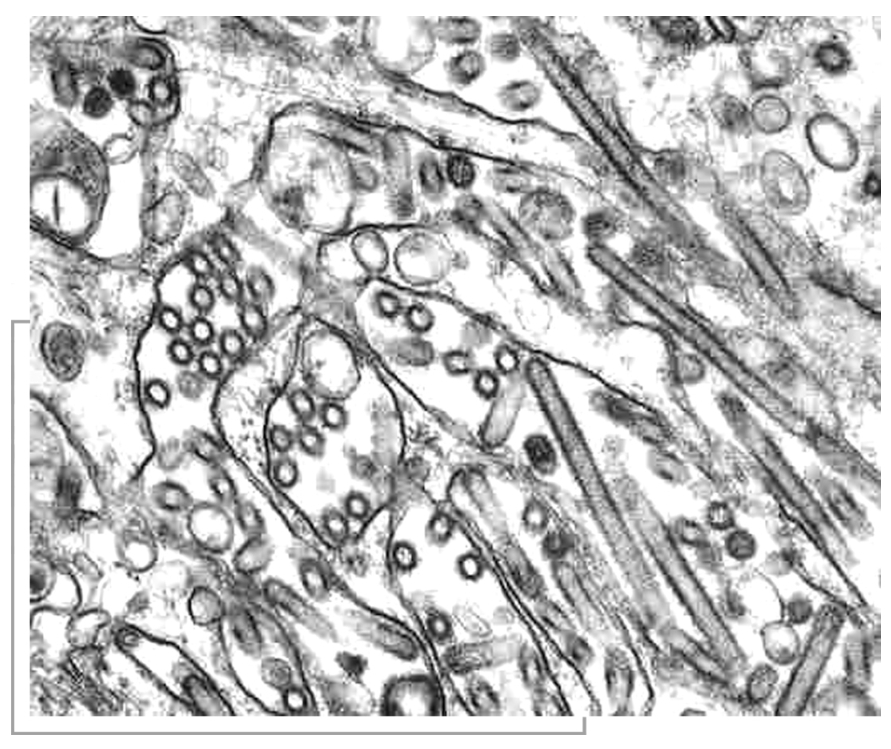

禽流感病毒(https://www.daowen.com)